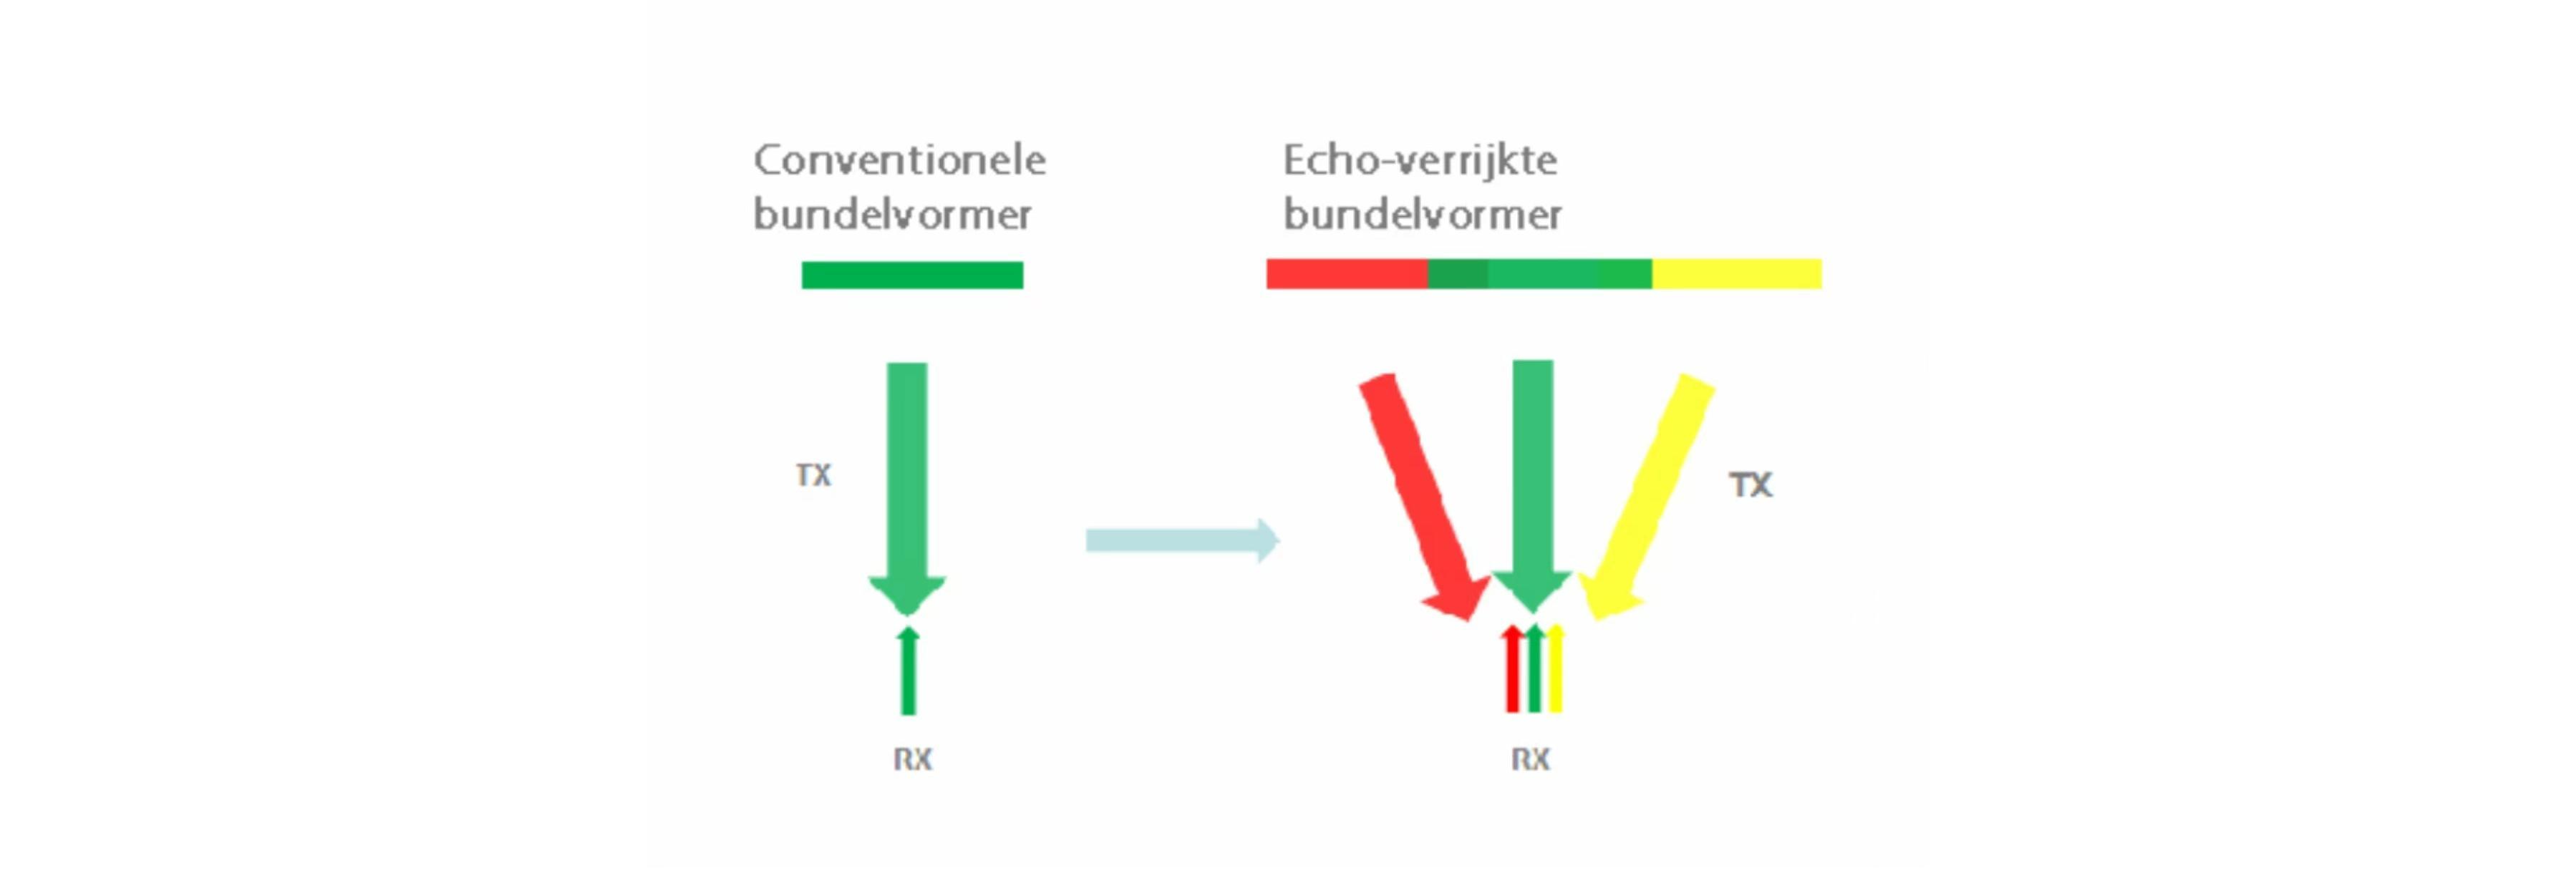

Echo-verrijkte Bundel Vorming

De echo-verrijkte bundelvorming combineert gewoonlijk verwaarloosde echosignalen van aangrenzende bundels voor een fijnere en sterkere beeldbundel, wat een beter 'out-of-focus' beeldresolutie en diepere beeldpenetratie oplevert.